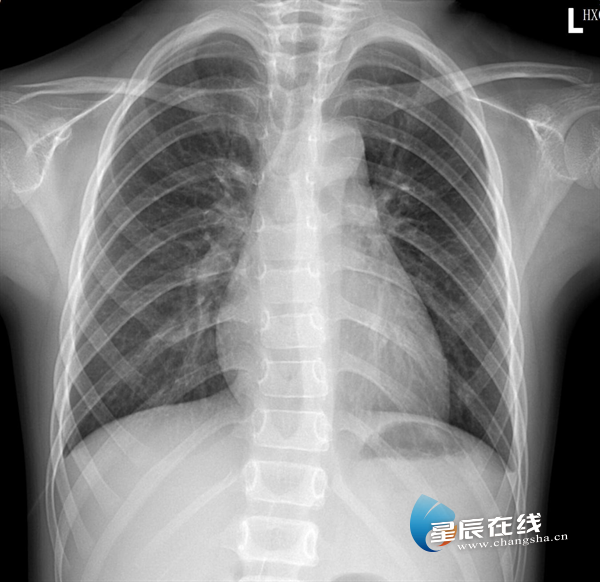

X光像一张透视照片,它利用X射线穿过人体,由于骨骼、肺部等组织密度不同,在片上形成黑白影像。这种鲜明的“黑白对比”能快速发现骨折、肺部感染等病变,速度快,常用于急诊和初步筛查。

(X光片影像示例,清晰显示骨骼与肺部的对比。)